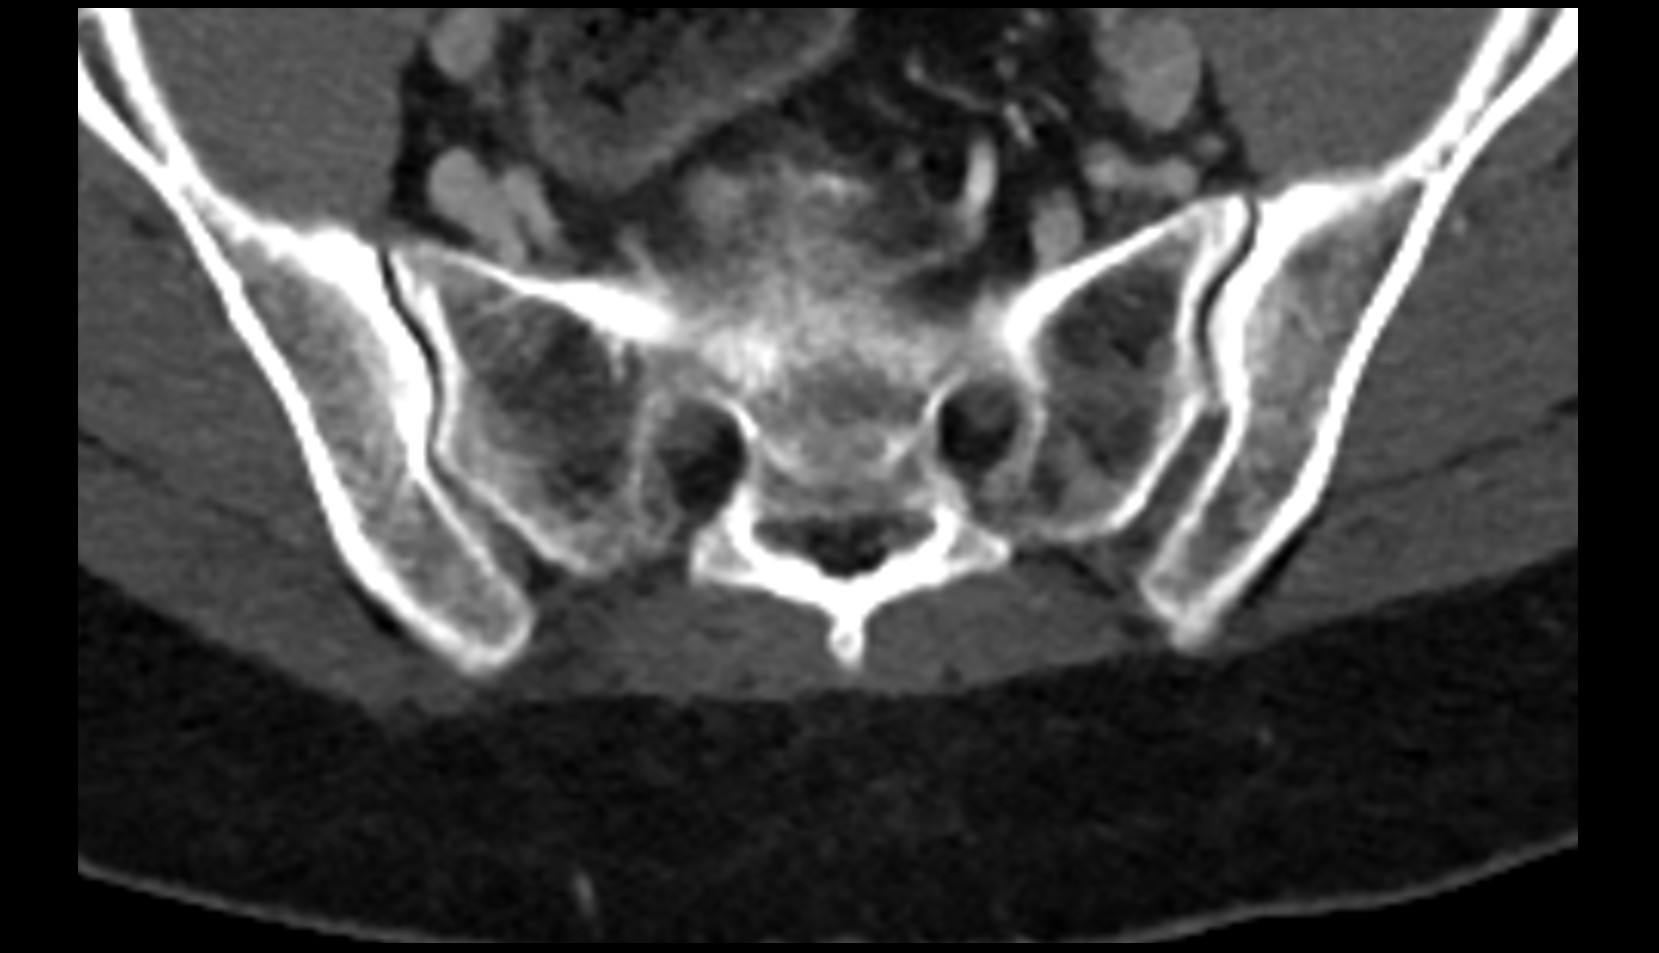

- Sacrum

- Sacroiliac joint

- Acetabular margin (Acetabular rim)

- Acetabulum

- Ilium bone

- Ischium bone

- Pubic bone

- Head of femur

- Neck of femur